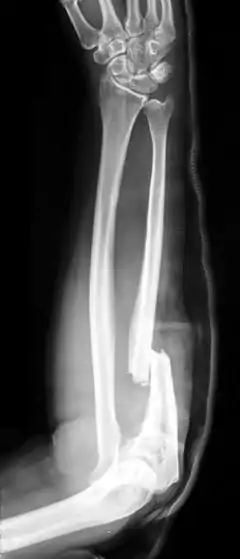

The Monteggia fracture is a fracture of the proximal third of the ulna with dislocation of the proximal head of the radius. It is named after Giovanni Battista Monteggia.[1][2]

| X-ray of Monteggia fracture of right forearm | |